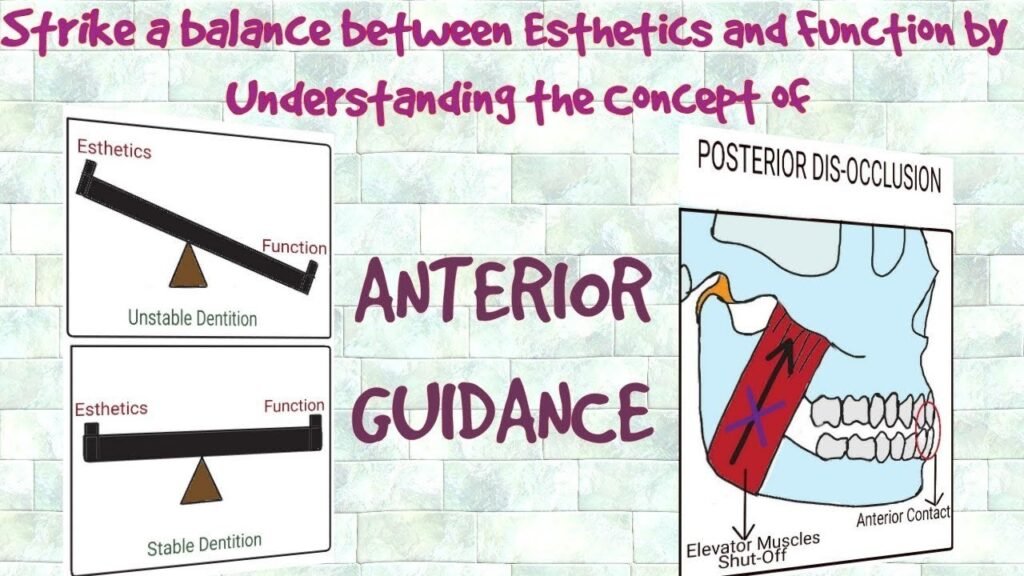

- Occlusal Analysis

- Dynamic Occlusal Considerations

- Anterior guidance patterns

- Envelope of function

- Parafunctional risk assessment

- Occlusal stability evaluation